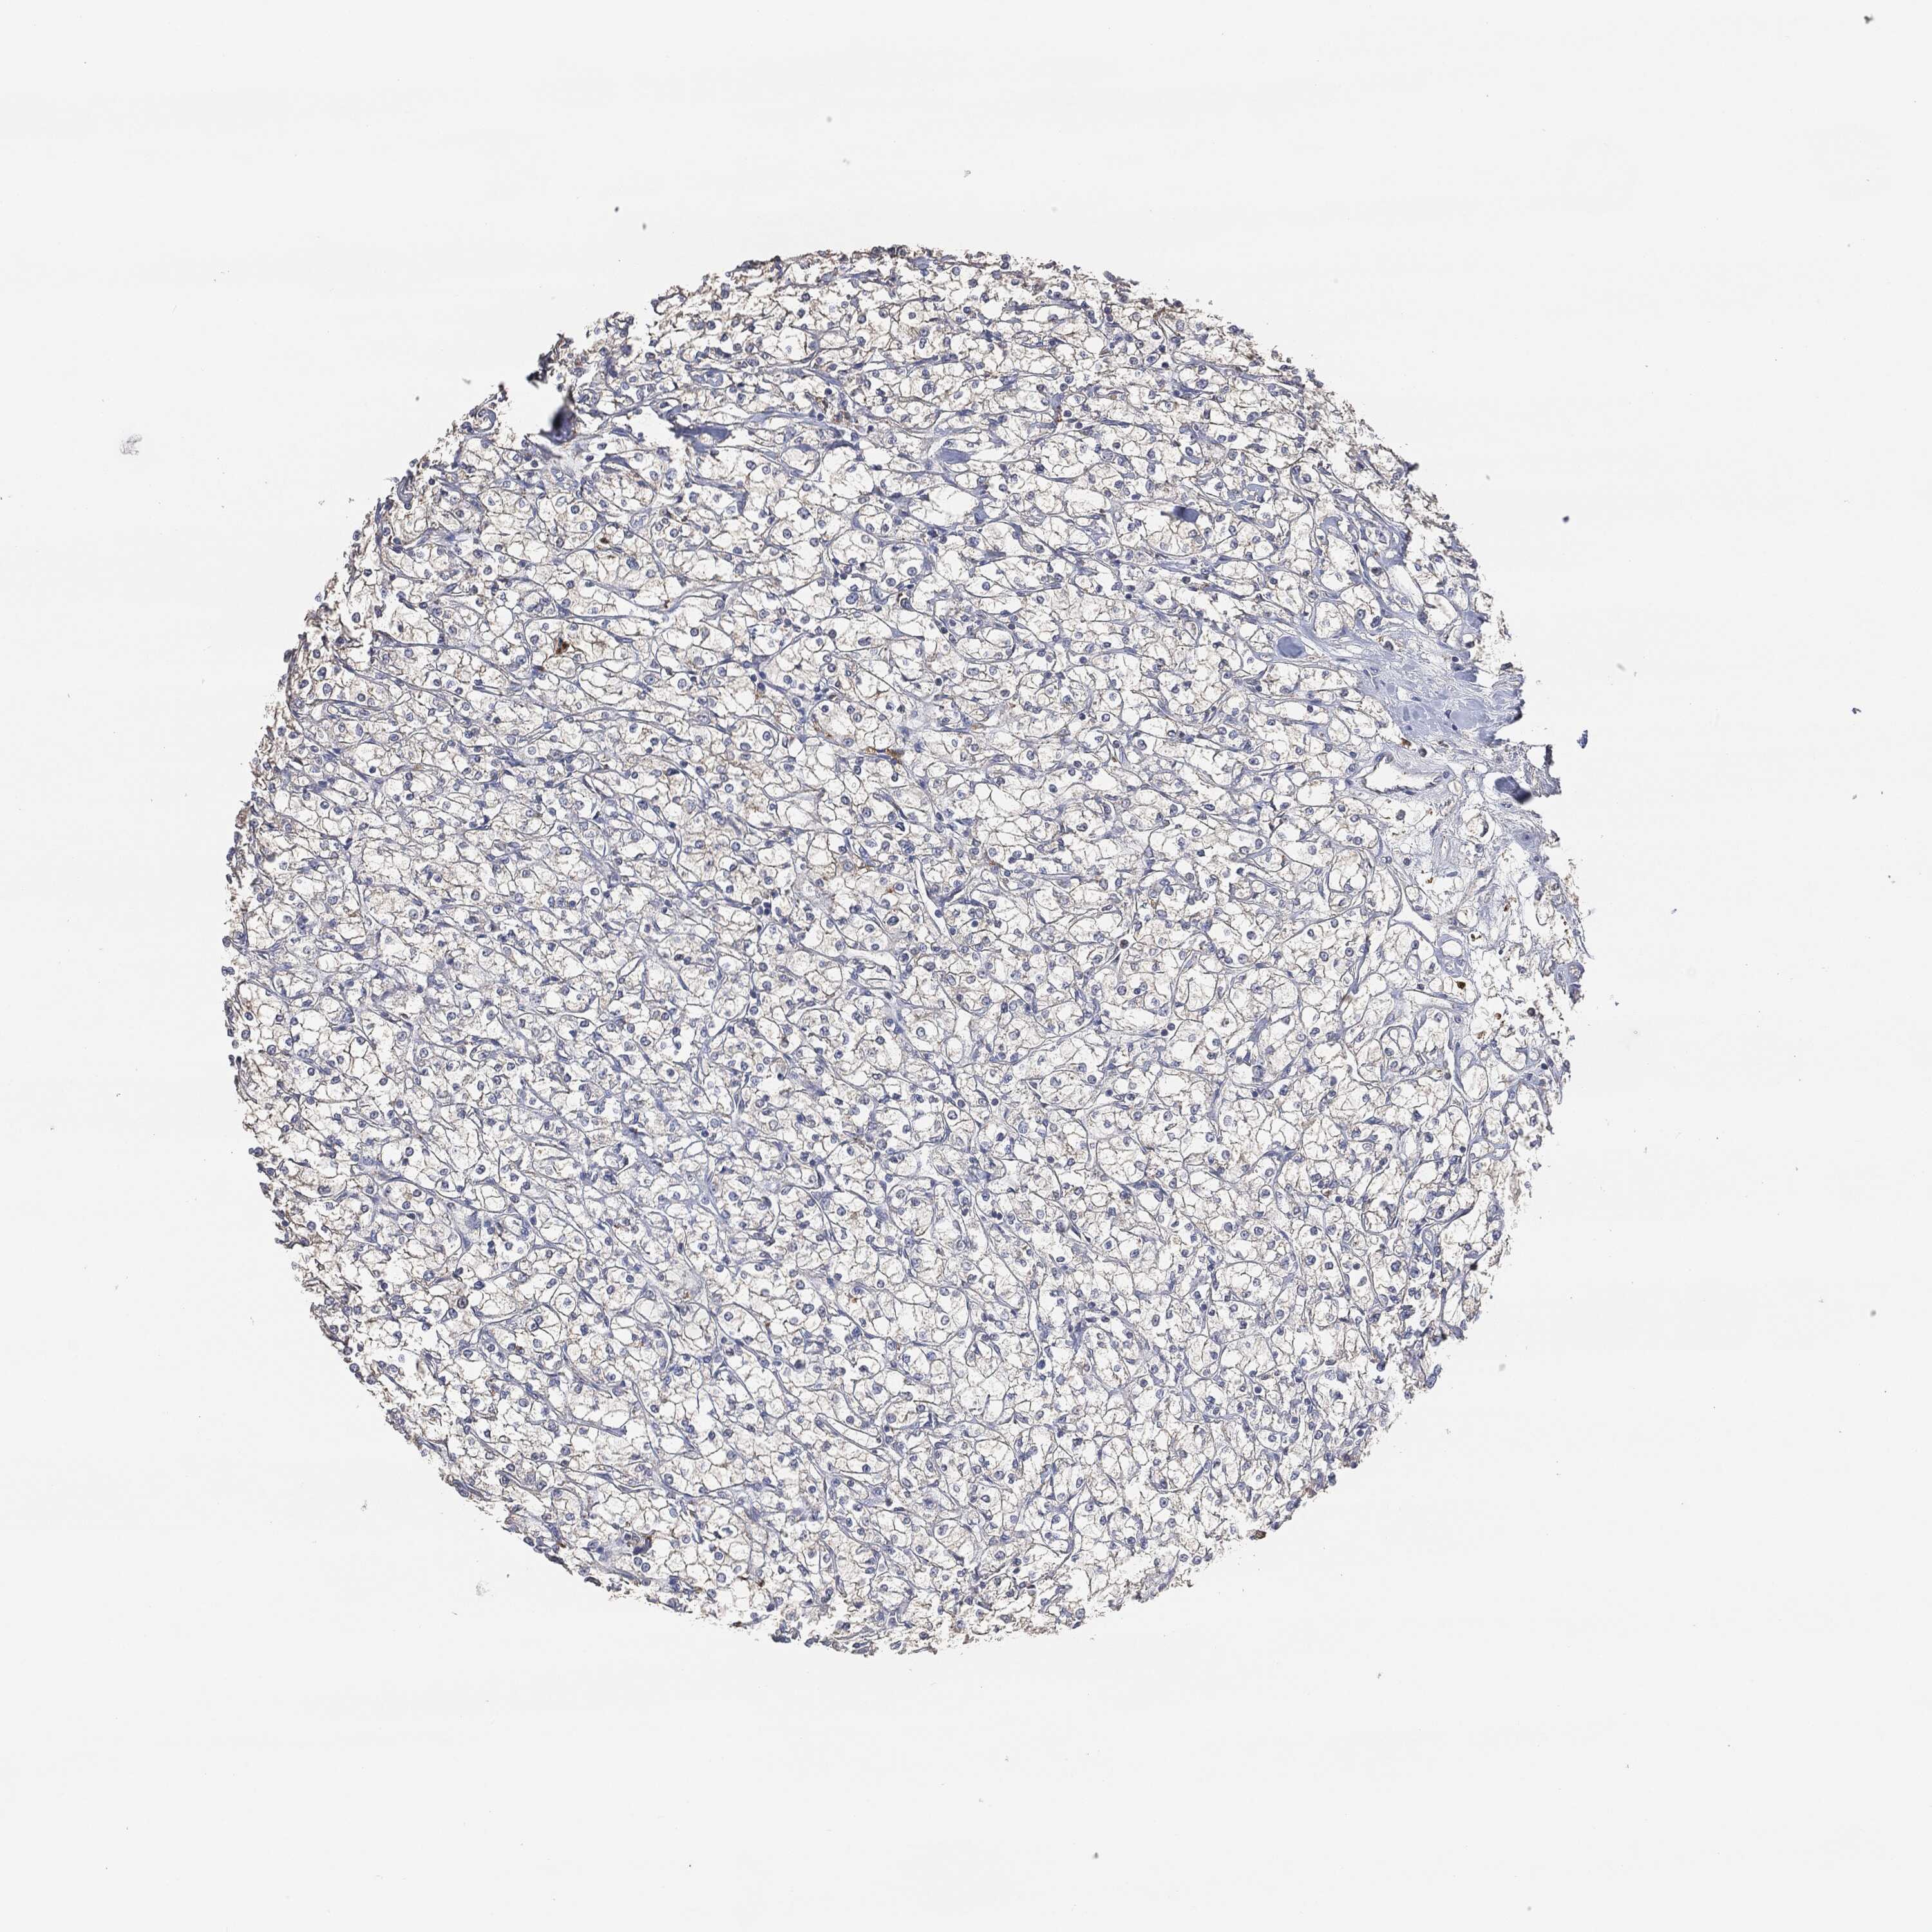

KIDNEY RENAL CLEAR CELL CARCINOMA (TCGA) - Interactive survival scatter ploti

The Survival Scatter plot shows the clinical status (i.e. dead or alive) for all individuals in the patient cohort, based on the same data that underlies the corresponding Kaplan-Meier plots. Patients that are alive at last time for follow-up are shown in blue and patients who have died during the study are shown in red.

The x-axis shows the expression levels (FPKM) of the investigated gene in the tumor tissue at the time of diagnosis. The y-axis shows the follow-up time after diagnosis (years). Both axes are complimented with kernel density curves demonstrating the data density over the axes. The top density plot shows the expression levels (FPKM) distribution among dead (red) and alive patients (blue). The right density plot shows the data density of the survived years of dead patients with high and low expression levels respectively, stratified using the cutoff indicated by the vertical dashed line through the Survival Scatter plot. This cutoff is automatically defined based on the FPKM cutoff that minimizes the p-score. The cutoff can be changed by dragging the vertical line or by entering a cutoff value in the square labeled "Current cut-off".

Under the Survival Scatter plot the p-score landscape (black curve; left axis) is shown together with dead median separation (red curve; right axis). Dead median separation is the difference in median mRNA expression between patients who have died with high and low expression, respectively. It is calculated as follows: median FPKM expression of dead patients with high expression - median FPKM expression of dead patients with low expression. This is intended to aid the user in visually exploring custom cutoffs and the associated p-scores and dead median separation.

Individual patient data is displayed and can be filtered by clicking on one or more of the category buttons on the top of the page. Categories describing expression level and patient information include: high, low, alive, dead, female, male and tumor stages. The scale of the x-axis can be toggled between linear and log-scale by clicking on the "x log" button. Mouse-over function shows TCGA ID, patient information and mRNA expression (FPKM) for each patient.

& Survival analysisi

Kaplan-Meier plots summarize results from analysis of correlation between mRNA expression level and patient survival. Patients were divided based on level of expression into one of the two groups "low" (under cut off) or "high" (over cut off). X-axis shows time for survival (years) and y-axis shows the probability of survival, where 1.0 corresponds to 100 percent.

EGFR is potential prognostic, high expression is favorable in Kidney Renal Clear Cell Carcinoma (TCGA)

Best expression cut offi

Based on the FPKM value of each gene, patients were classified into two groups and association between prognosis (survival) and gene expression (FPKM) was examined. The best expression cut-off refers the FPKM value that yields maximal difference with regard to survival between the two groups at the lowest log-rank P-value. Best expression cut-off was selected based on survival analysis .

When clicking on this number, the vertical dashed line indicating cut-off, the interactive survival plot, and the Kaplan-Meier curve will be adjusted to show results based on the best expression cut-off.

: 29.68

P scorei

Log-rank P value for Kaplan-Meier plot showing results from analysis of correlation between mRNA expression level and patient survival.

N/A

TCGA RNA samplesi

RNA-seq data is reported as average FPKM (number Fragments Per Kilobase of exon per Million reads), generated by the The Cancer Genome Atlas (TCGA) .

Normal distribution across the dataset is visualized with box plots, shown as median and 25th and 75th percentiles. Points are displayed as outliers if they are above or below 1.5 times the interquartile range. FPKM values of the individual samples are presented next to the box plot.

Average pTPM 52.9

Number of samples 521